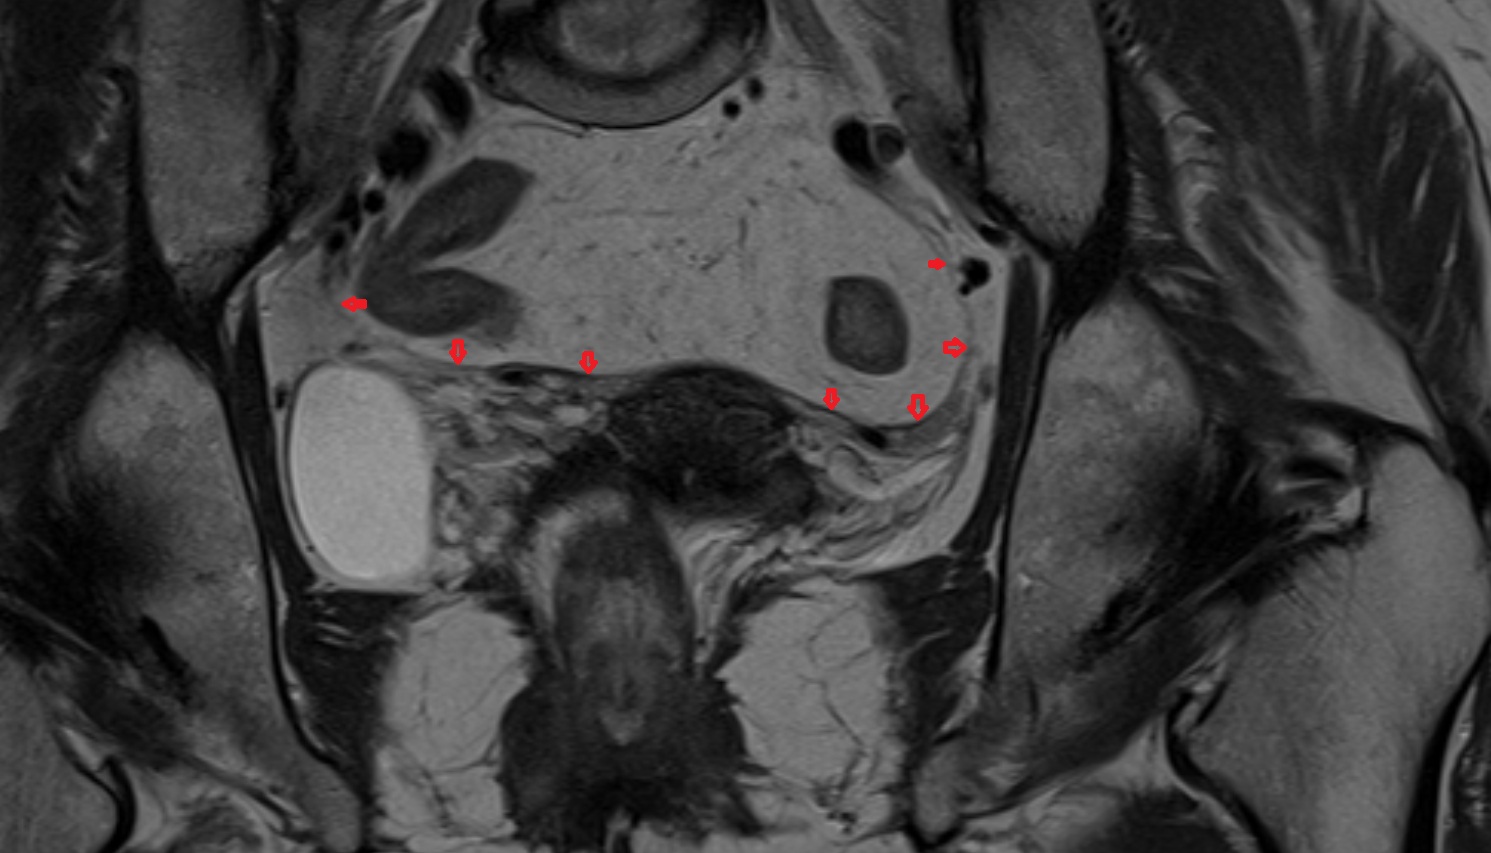

- Mesorectal fascia

- Mesorectum

- Uterus

- Ovaries